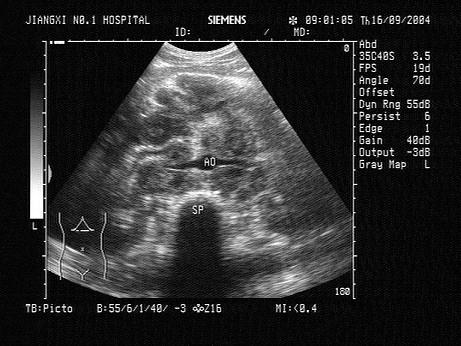

问题 患者,低热,清洁灌肠后,中腹部超声声像图可见融合成团的异常光团,最可能的诊断是?(?)

选项 A.胰腺癌 B.淋巴瘤 C.结肠癌 D.腹腔结核 E.腹膜后肿瘤

答案 B